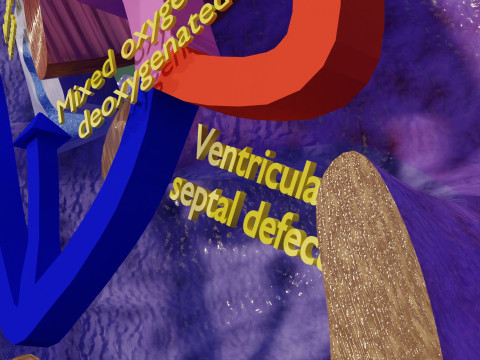

The model meshes include adult circulation versus circulation in Tetralogy of Fallot (TAF), arrow labels and text labels. The blood flow in a patient with Tetralogy of Fallot is outlined in this model. To contrast it to normal blood circulation a separate model of normal circulation is included. The Tetralogy of Fallot (OVER RIDING OF AORTA, PUL STENOSIS, VENTRICULAR SEPTAL DEFECT, RIGHT VENTRICULAR HYPERTROPHY), fossa, ligament teres , venosus, and arteriosus are duly depicted with proper labelling and blood flow directional arrows. Excellent model for teaching, demonstration and knowlegde of human body. The models include both procedural and image textures blend files separately. The texture file include diffuse, roughness and normal png and jpeg based on non overlapping UV maps.